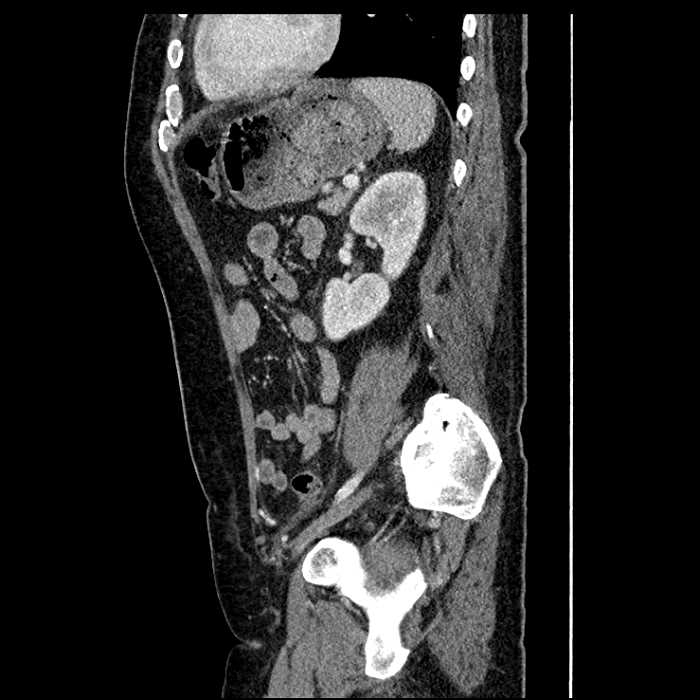

• Large fluid density structure in hepatic segments 7 and 8 measuring 10 x 7 x 7 cm with internal septation and circumferential ill-defined low density compatible with edema

• Peripherally enhancing subcapsular collections along the anterior margin of the left hepatic lobe measuring 3 x 1 cm and 2 x 1 cm

• Clearly marginated fluid density structure in segment 7 and several other scattered tiny hypodensities, which likely represent cysts

• Mild mural thickening of a segment of the sigmoid colon with adjacent fat stranding and a 1.5 cm fluid and gas collection along the tip of an inflamed diverticulum

• Loss of the normal fat plane between this collection and adjacent loops of small bowel, which demonstrate mural thickening

Acute sigmoid diverticulitis complicated by a small contained perforation and a large abscess in the right hepatic lobe. Additional small subcapsular abscesses along the anterior margin of the left hepatic lobe.

Additionally, loss of the normal fat plane between the peridiverticular collection and adjacent thickened loops of small bowel raises the potential for an enterocolonic fistula.

• The classic CT imaging appearance is a double target sign with internal low density surrounded by an internal enhancing rim (capsule) and a low density external rim (edema)

Hepatic abscess showing the double target sign with low density internally surrounded by a thin inner enhancing rim (red arrow) and ill-defined outer low density rim (yellow arrow). Blue arrow indicates an internal septation. Red arrows: additional smaller subcapsular abscesses. Red arrow: focal contained perforation associated with diverticulitis.